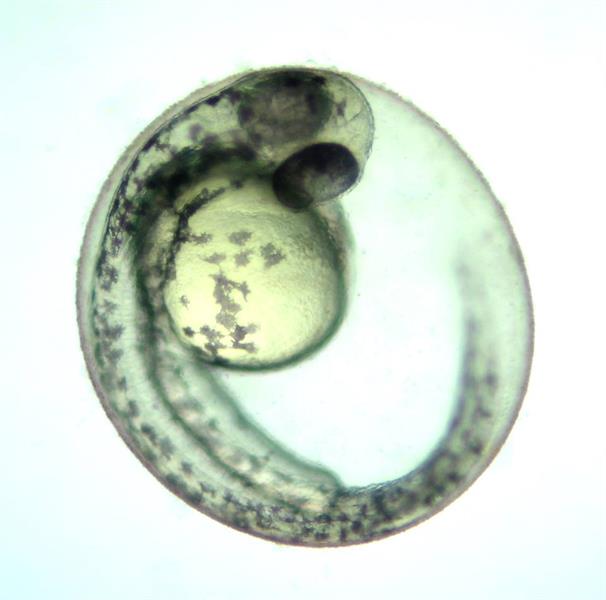

Pesquisa desenvolvida na UPF constatou que os resíduos de medicamentos afetam o comportamento das larvas de peixe e interferem o seu desenvolvimento. Trabalho foi publicado na Scientific Reports do Grupo Nature

Não é de hoje que os pesquisadores têm voltado seus olhares para as reações da natureza frente às ações do ser humano. Exemplo dessa preocupação é a pesquisa “Psicotrópicos no meio ambiente: os resíduos de risperidona afetam o comportamento das larvas de peixe”, desenvolvida por alunos e professores da Universidade de Passo Fundo (UPF), Universidade Federal de Santa Maria (UFSM) e Universidade Federal do Rio Grande do Sul (UFRGS). O trabalho, que mostra como a presença de resíduos do medicamento pode alterar o comportamento exploratório dos embriões e larvas do zebrafish, foi publicado na Scientific Reports, uma das revistas do Grupo Nature.

Os pesquisadores destacam que a capacidade de evitar e escapar de predadores contempla comportamentos fundamentais vistos da perspectiva ecológica e interfere diretamente na sobrevivência dos organismos. Detectada no meio aquático, a risperidona pode alterar esse repertório de comportamentos nas espécies expostas. Considerando o risco de exposição nos estádios iniciais da vida, a equipe submeteu embriões de peixe-zebra à risperidona durante os primeiros cinco dias de vida. O resultado apontou que a risperidona causou hiperatividade nas larvas expostas, o que, em um contexto ambiental, pode fazer com que os animais fiquem mais vulneráveis à predação devido à maior visibilidade ou à menor percepção de áreas de risco.

De acordo com ela, a pesquisa mostrou que a risperidona não só coloca em risco a vida dos embriões expostos como também muda o comportamento desses animais, deixando eles hiperativos. Ela explica que o zebrafish se desenvolve muito rapidamente e em apenas cinco dias de vida as larvas já nadam ativamente em busca de abrigo (fugindo dos predadores) e à procura de alimento para sua sobrevivência. “Fizemos a exposição à risperidona durante esse período e percebemos que os peixes passaram a ter um comportamento diferente em relação aos não expostos, ficando menos atentos ao ambiente e explorando áreas onde seriam perigosas a eles. Também mostraram alguns sintomas da hiperatividade, o que, do ponto de vista ecológico, pode deixar eles mais expostos a predadores e ainda gerar um gasto de energia desnecessário”, pontua.